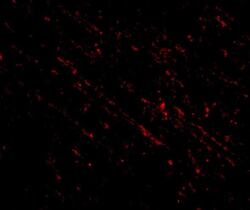

PA5-20557 IHC

Method:

Other validation